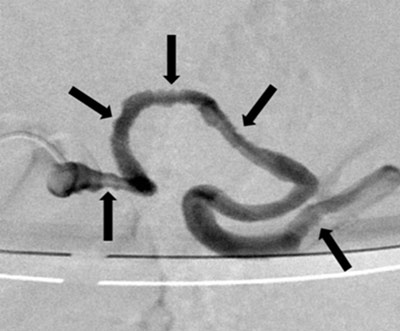

Figure 2a

Selective splenic artery opacification: the multiple parietal irregularities (arrows).

Figure 2b

Postostial occlusion of the splenic artery: the 5F support catheter (thin arrow), the 3F microcatheter (thick arrow), and the microcoils (star).